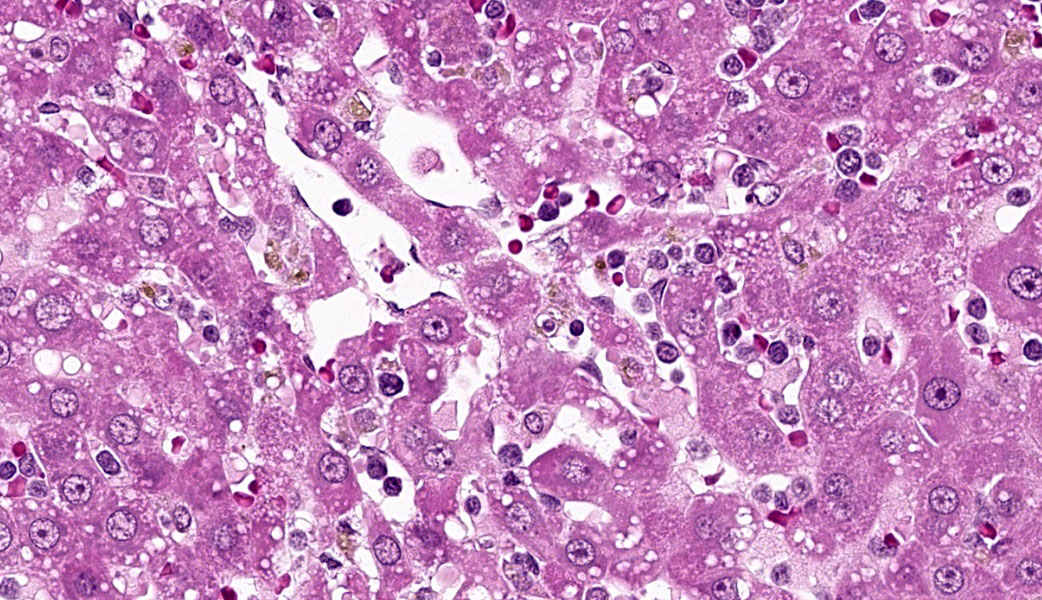

Microscopic Description:

Liver: Diffusely filling portal veins and expanding sinusoids is a neoplastic population composed of round cells with distinct cell borders, small amount of eosinophilic, granular cytoplasm, round to occasional reniform nucleus, clumped chromatin and indistinct nucleolus. Mitotic rate is <1 per hpf.

Diffusely centrilobular hepatocytes are lost, degenerating or necrotic. Diffusely there is lobular atrophy and sinusoids are expanded by previously described neoplastic cells admixed with eosinophilic cellular debris. Multifocally centrilobular kupffer cells and/or hepatocytes contain hemosiderin pigment. Multifocally within portal regions there is an increase in small bile duct profiles (ductular reaction). Rarely, bile duct epithelial cells are degenerative, necrotic or undergoing regeneration.

Contributor's Morphologic Diagnoses:

Liver: Leukemia, large granular lymphocytic

Conference 19 was moderated by the esteemed Dr. Kimberly Whitten, a veteran Department of Defense laboratory animal toxicological pathologist who works for USAMRICD. This first case was a classic entity in F344 rats and one that must be at the forefront of any pathologist's mind in this strain. LGL leukemia in F344 rats closely resembles the NK-cell leukemia seen in humans and, as such, they are used as a research model for this aggressive disease.7 Morphologically, the LGL leukemia cells resemble normal rat LGLs, but there are notable differences in cytotoxicity & surface antigens. Normal rat LGLs usually express surface markers such as CD8, CD2, CD56, and ASGM1, while leukemic LGLs tend to show abnormal or low-level expression of T-cell receptor (TCR) beta chains, may or may not express ASGM1, and can display heterogeneity in markers like CD56.7,9 This suggests that these leukemias may be of a heterogeneous lymphocytic origin, although NK-cell markers predominate.7,9